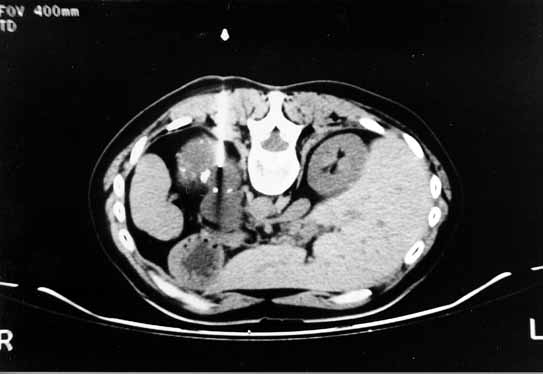

Figura 5: Caso 2. Cavidad quística de paredes gruesas.